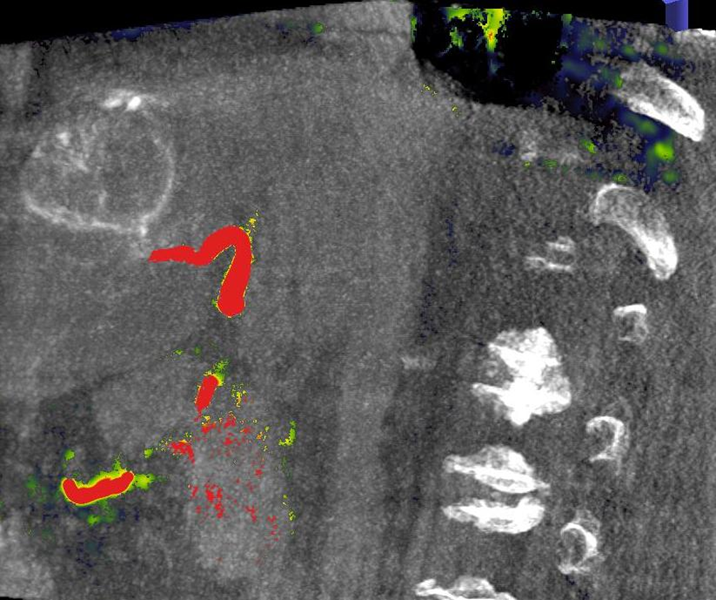

Die Selektive Interne Radiotherapie (SIRT) wird in der Fachliteratur auch Radioembolisation (RE) genannt. Hierbei werden gezielt kleine, radioaktive Kügelchen, sog. Mikrosphären, über den Katheter (siehe TACE) von mehreren Positionen in der Leber mit dem Blutstrom in das gut durchblutete Tumorgewebe gebracht und bleiben dort in den kleinen Gefäßen "stecken", die den Tumor ernähren. Von dort bestrahlt das in den Kügelchen enthaltene radioaktive Element Yttrium-90 über mehrere Tage hinweg das Tumorgewebe und zerstört es selektiv. Dieses Verfahren kann bei Leberkrebs oder -metastasen eingesetzt werden, wenn die Herde trotz Chemotherapie weiter wachsen und nicht chirurgisch oder mittels RFA und TACE behandelbar sind.

Das Verfahren wird von der interventionellen Radiologie zusammen mit der Partnerabteilung der Nuklearmedizin sowie den entsprechenden Partnerkliniken geplant und durchgeführt.

Abbildung Körper: Schematische Darstellung des Zugangsweges bei SIRT-Therapie über die Leistenarterie. Die arteriellen tumorversorgenden Gefäße in der Leber werden selektiv dargestellt und von dort wird die Therapie lokal appliziert. (Bildrechte beim Thieme-Verlag!)